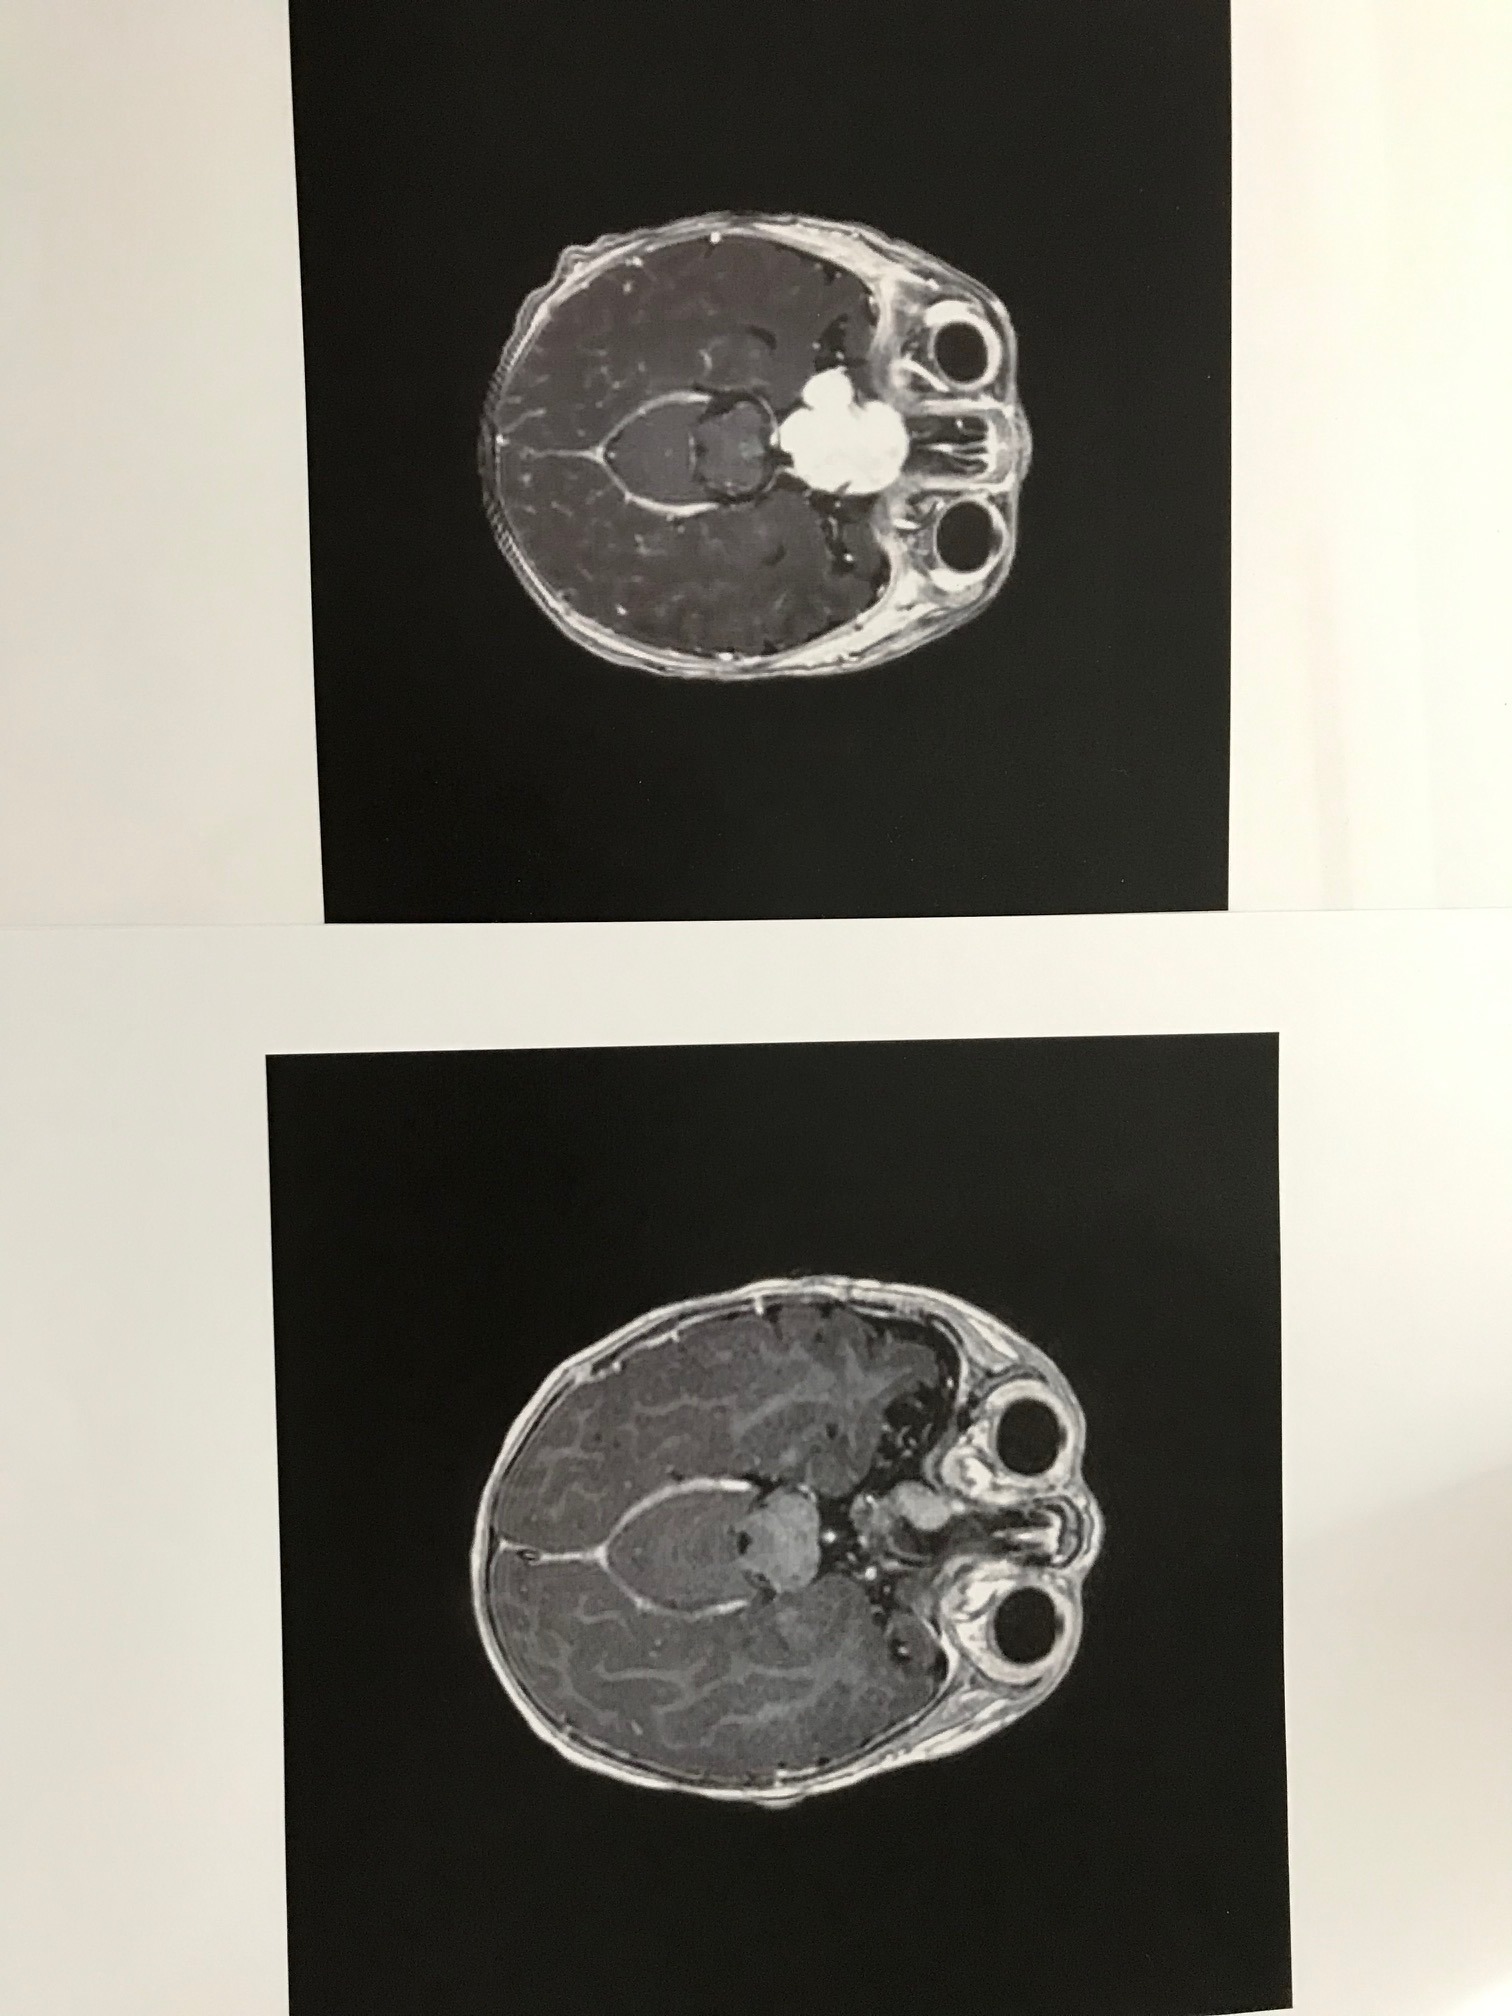

Our daughter Ellie is 6 years old. She has been fighting a brain tumor, a glioma with a BRAF gene fusion, for her entire life. She's visually impaired from it.

Recently we received the devastating news: the tumor grew by 20% in 2 months, while under treatment. And we have now reached the end of available treatment options in Sweden for Ellie.